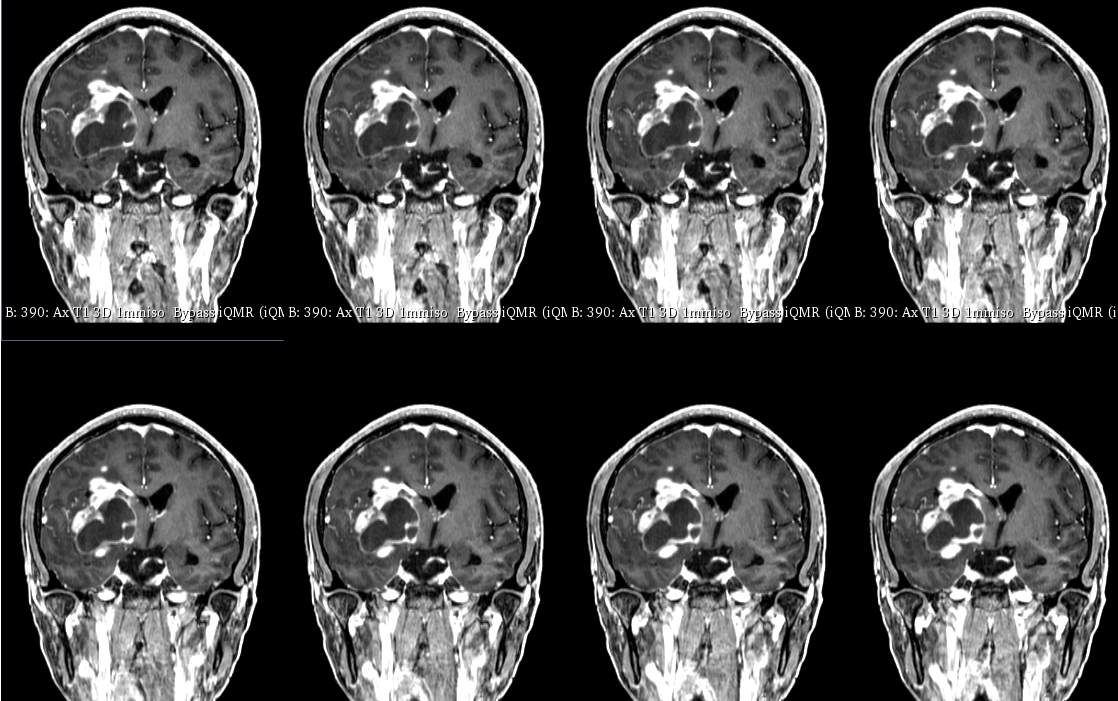

入院后于当地医院完善头颈部CTA检查未见明显血管发育异常,于2023-6-7行血肿钻孔引流术+脑室内颅内压监护探极置入术,引流一周后拔除引流管,期间未行尿激酶注射,患者反应情况逐渐好转,肌力未见明显改善。于出血后3周左右脑水肿基本消退后出院行康复治疗,治疗过程中患者肌力曾有所改善,左侧肢体肌力最好可达3级。术后3月左右患者一般状态逐渐变差,无发热,神志逐渐进展为昏睡状态,左侧肢体肌力1级,复查颅脑CT示水肿较前明显加重,颅脑MRI示右侧基底节区长T1长T2团块状病变,内有囊变,呈不均匀菜花样强化,考虑为高级别胶质瘤可能性大。遂行开颅病灶大部切除+去骨瓣减压术,术后病理提示高级别胶质瘤伴囊变,后续行同步放化疗STUPP方案,PTV:60Gy/30F/6周,替莫唑胺350mg化疗。患者右侧基底节区病灶相对稳定,2024-9-3复查颅脑MRI可见脑室内新发病灶。患者目前KPS 60分,神志清醒,精神差,反应迟钝,语言对答部分切题,右侧肢体自主活动,左侧肢体肌力2级。